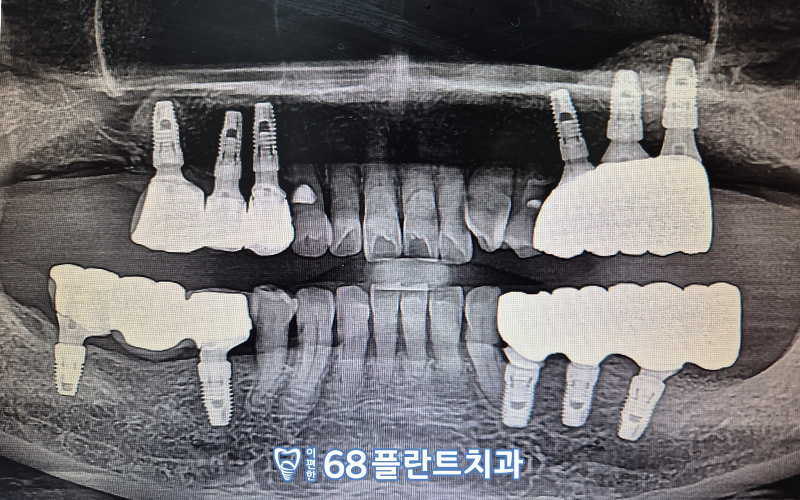

오늘 소개해드릴 분께서는

왼쪽 임플란트 상.담을 위해

본.원을 찾아주셨는데요.

오른쪽 어금니 부위엔

위아래로 임플란트가

식립되어 있는 상태였고,

왼쪽 어금니 부위는

위의 첫번째 작은어금니를 제외하고

구치부가 전부 상실된 상태였습니다.

그런데 치아가 상실된 지 오래되어

잇몸뼈라인이 많이 내려가 있는 상황이었는데요.

잇몸뼈가 많이 부족한 상황이라

뼈이식을 병행하여

임플란트 식립을 계획하였답니다.

수술 전 CT 사진을 통해,

잇몸뼈의 양, 인접치들과의 관계,

상악동과 신경관의 위치 등

여러가지 구강 내 상황을

면밀하게 체크한 후

식립할 위치 및 방향을 사전에 계획하여

수술을 진행하였습니다.